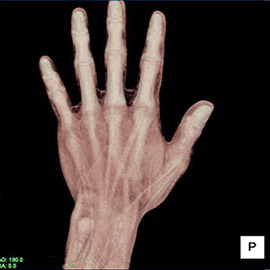

80列マルチスライスCTで撮影した画像

整形